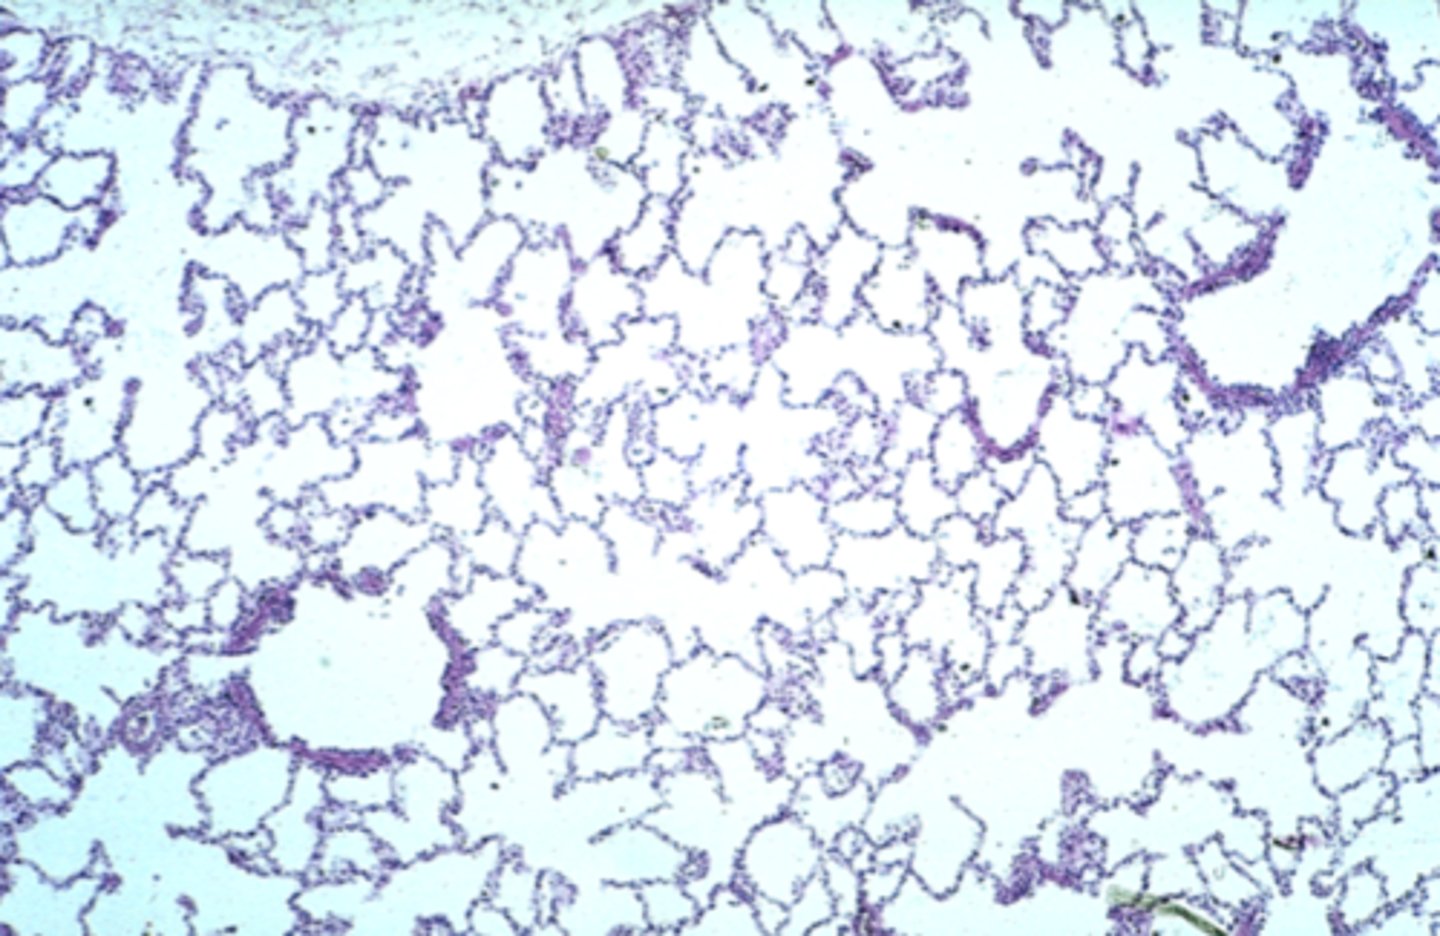

lung

What is this?

lung

What is this?